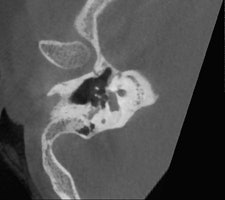

"If the problem is related to conductive hearing loss, then it is most likely to be in the middle ear, in the ossicles, and this requires a CT scan or a conebeam CT. But if the hearing loss is sensorineural, you need to use MRI," stated De Foer, adding that the clinical history of the patient and the clinical examination also will help in choosing the appropriate imaging technique.

He is an advocate of conebeam CT, which is growing in popularity, and recounted the advantages of conebeam CT over conventional CT. He said that he previously conducted all temporal bone imaging on a multidetector-row CT, but he now uses conebeam CT far more frequently. It is different because he uses a flat-panel detector, which provides a high resolution, he explained. Images scan at 0.1-mm resolution, whereas multidetector-row CT scans at 0.5 mm to 0.6 mm.

Several of De Foer's patients were initially scanned on multidetector-row CT and returned postsurgery to receive a conebeam CT. The detail on a conebeam CT is much greater, and the dose is also eight to nine times lower with conebeam in our study of it, he said.

"The level of detail of the ossicular chain is better. For example, the footplate detail is clearer," he said. "The facial nerve running through the middle ear has a bony coverage which is hardly visible on multidetector CT but is very visible on a cone-beam; likewise, the bony covering of the superior semicircular canal, which is important in the Tullio phenomenon."

De Foer also described how conebeam CT is particularly suitable for otosclerosis. This pathology relates to a demineralization of the bone in the inner ear, which prevents the stapes from conducting sound. Conebeam CT shows this in more detail than multidetector-row CT, especially in the evaluation of the footplate.